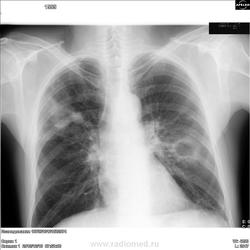

Прямо с приёма терапевта,с утра пораньше мужички с кашлем и субфебрилом 2 недели.Поразмыслим?

Не буду томить:первому поставил центральный рак справа и мтс, второму-диссеменированный туберкулёз в фазе распада.На следующей неделе сверка с онкологом и ПТД.

1. Вначале написал бы пневмонию. Спарава жидкость есть. Слева или осумкование идёт, или утощение плевры в месте перелома.

Ага, я бы тоже написала у первого мтс и правосторонний выпот, а второму тбц - на полостные метастазы не тянет, очень уж положение изменений "туберкулезное"

Попралю себя - со второго взгляда в первом случае все же ателектаз нижней доли..

Мнение по первому случаю: перелом ключицы слева и трех ребер (причем перелом со смещением заднего отрезка 7-го ребра с намеком на гематому) - на первое место; нижнедолевую пневмонию справа - на второе. Гиповентиляция справа обусловлена травмой противоположной половины грудной клетки.

Я думаю, что в первом случае - правосторонняя деструктивная пневмония, осл.плевритом, а слева паракостальный осумкованный плеврит.

Наизусть уже не помню,но про первого-правое лёгкое уменьшено в объёме,в нём-округлые фокусные тени(симптом "монет").По второму-фокусная теннь справа в верней доле, полость в шестёрке слева,соотв. конс онколога первому,фтизиатра-второму.Информация по дообследованиям будет на след. неделе-годовая сверка,сообщу обязательно.

По первому случаю.

Конечно, "симптом монет", или "разменной монеты", есть и другие вариации обозвать данную скиалогию, заставляет прежде всего подумать о "мета", но это прежде всего...

Коллеги высказывались за переломы. Дмитрий указал и на перелом ключицы. Не знаю, свежий там перелом, или давно он её сломал. Но странно, что никто не провёл сломанное 7 слева ребро. Я часть его контура так и не нашёл. Думаете такая мягкотканная у него мозоль наросла по внутренней поверхности того ребра? Сомневаюсь. Сильно сомневаюсь в этом я. Мягкотканный компонент mts - больше похоже - добавлю, и в этот раз - на мой взгляд.